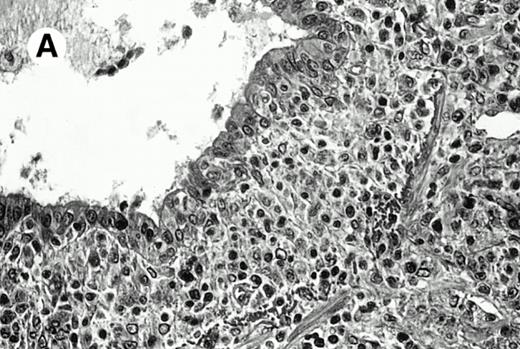

Three cases (cases no. 1 to 3) were located in the nasal cavity. The neoplastic infiltrate consisted of medium and/or large pleomorphic lymphoid cells (Fig 1)intermingled with variable numbers of small lymphoid cells, plasma cells, eosinophils, and histiocytes. Features of angiocentrism and angioinvasion, epitheliotropism, and areas of necrosis were observed in all three cases. Patient no. 4 presented with disease restricted to the lung and an open-lung biopsy was available. The neoplastic infiltrate was composed of large atypical lymphoid cells and was predominantly interstitial without extensive destruction of the normal architecture. Features of angiocentrism, angioinvasion, and epitheliotropism were present (Fig 2A and B). Case no. 5 involved the larynx, extending to the piriform sinus, the ventricle, and the arytenoid. One month later, the lymphoma disseminated to the subcutaneous tissue in the spinal region and biopsy specimens from both sites were available. The neoplastic cells were medium and large, with abundant clear cytoplasm and slightly irregular nuclei with dense chromatin. Epitheliotropism was present in the larynx mucosa. Small foci of necrosis and angiocentrism were seen without angioinvasion. Three patients presented with cutaneous disease. Cases no. 6 and 7 were comparable, as both histories started with necrotic subcutaneous nodules of the thigh, which on histologic analysis were characteristic of cytophagic histiocytic panniculitis without evidence of lymphoma (Fig 3A). Second excisional biopsies of cutaneous nodules obtained 7 and 5 months later, respectively, showed characteristic features of lymphoma in both cases (Fig 3B). However, in case no. 6, skin biopsy specimens showed an epidermotropic PML lymphoma extending to the dermis and the subcutaneous tissue, whereas in case no. 7, the neoplastic infiltrate consisted of a PSC confined to the subcutaneous tissue, admixed with benign histiocytes that showed phagocytosis. Patient no. 8 presented with recurrent skin lesions with spontaneous remission over a period of 10 years. The initial skin biopsies demonstrated an intense epidermotropic neoplastic infiltrate that extended to the superficial and deep dermis composed of atypical PML cells. All cutaneous cases displayed features of angiocentrism, but angioinvasion was observed only in case no. 6 and foci of necrosis in cases no. 6 and 8.

Pleomorphic large-cell γδ T-cell lymphoma (case no. 3) (nasal biopsy specimen with hematoxylin-eosin stain).